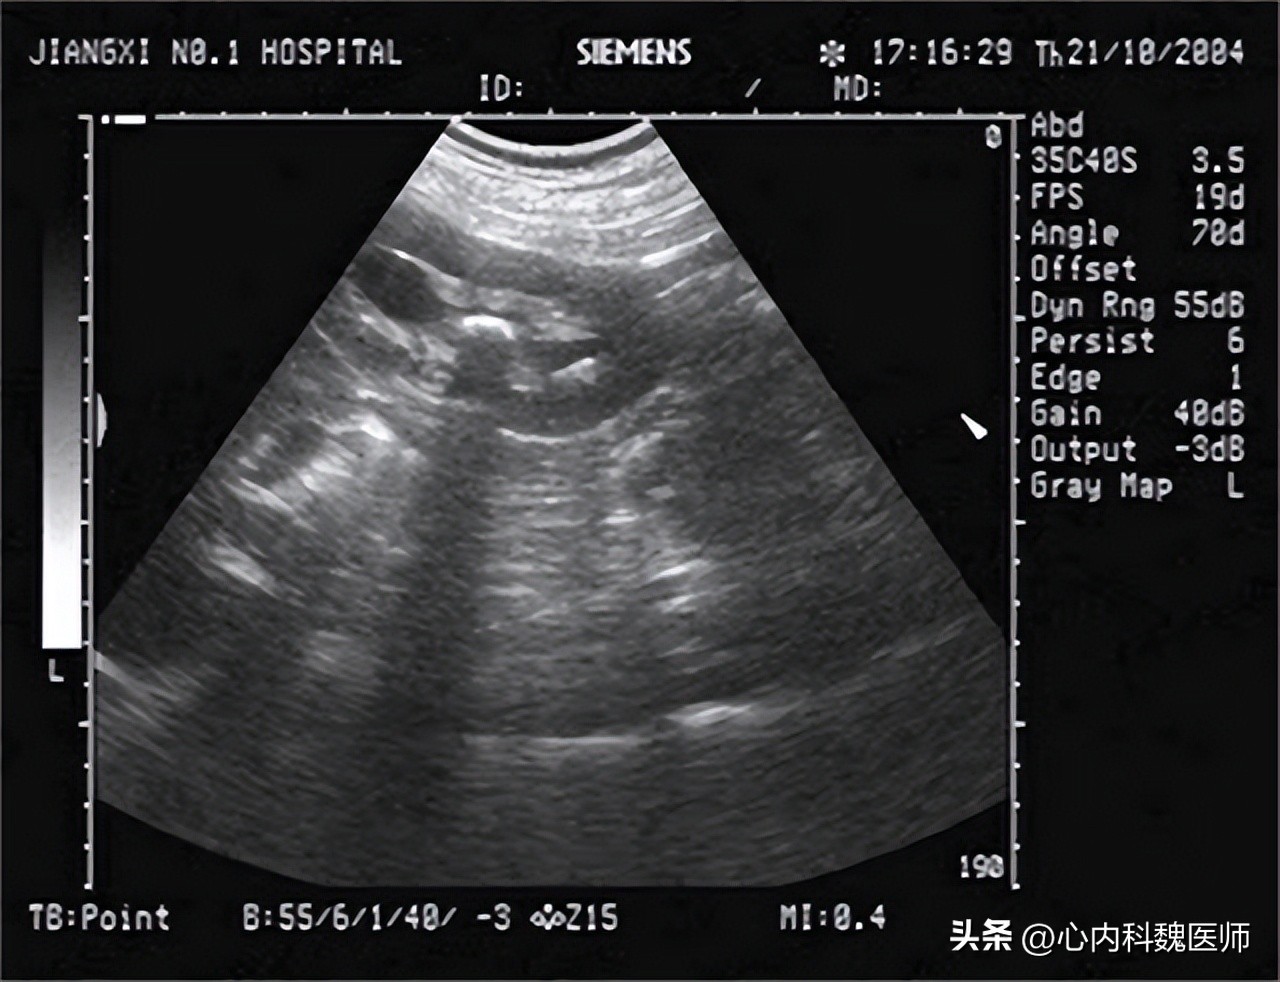

医生听完李大爷的自述,盯着那瓶降压药看了半天, 上面赫然写着苯磺酸氨氯地平片,便连忙安排让李大爷去做尿常规检查还有肾脏B超检查, 检查结果一出来,医生就对李大爷说道:您这是擅自换降压药导致的 肾衰竭 ,幸亏就医早,不然后果不堪设想。您看,您的 尿蛋白都三个加号了,还有尿肌酐值也到150umol/L了,肾脏B超也提示双肾体积减小 ,再联系您最近的临床症状,这就是肾衰。